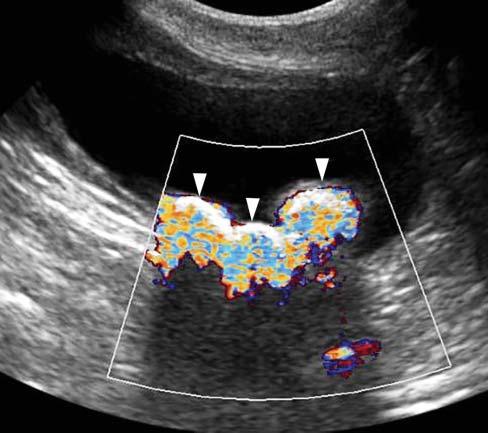

With colorDoppler,acolormapisusedtodisplay thedirectionandvelocityofthebloodflow.Thesize

Figure1.11. ColorandpowerDopplermodes.A: WithcolorDoppler,thedirectionofbloodflowcanberapidlydetermined. Inthisdog,therightexternaliliacartery(a)andvein(v)showredandbluecolorhues,indicatingflowsdirectedtoward andawayfromtheprobe,respectively. B: Colorhuecanchangeinthesamevesselduetoachangeindirectionoftheflow, asdemonstratedinthistortuousportosystemicshunt(PSS).Thearrowsindicatethedirectionoftheflowthroughthatshunt. Whentheflowbecomesperpendiculartotheprobe,asignalvoid(*)appearsbecauseofthelackofDopplershift.PowerDoppler maybecomeusefulinsuchcircumstance. C: PowerDopplerhelpstodistinguishthisdilatedcommonbileduct(arrowhead) inacatfromthenearbyportalvein(PV)andcaudalvenacava(CVC). D: PowerDopplermayalsobeusedtodetectaureteral jetcomingfromapatentureter,asopposedtotheipsilateralureterwhichisobstructedbyasmallurolith(arrowhead).

andlocationoftheinterrogationboxareadjusted toprovideanoverallviewoftheflowinagiven region,andsuperimposedontheB-modeimagefor anatomicallocalization.ColorDopplerisessentialfor cardiacevaluation(seeChapter5),butcanalsoserve intheassessmentofotherbodyparts.Itallowsrapid identificationofvesselsandevaluationoftheirflow characteristics,aswellasdetectingaberrantvessels suchasportosystemicshuntsorarteriovenousfistulas andassessingtissueperfusion ColorDopplermode

PowerDoppler –alsoknownasenergyorangioDoppler–ismoresensitivetoflowsoflowvelocity asitdisplaysthesummationofalloftheDoppler shiftsignalsratherthanthemeaninagivenarea. Thismodeisfavoredforconfirmingorinformingthe presenceofbloodflow,particularlyinsmallervessels, ortodifferentiatebloodvesselsfromothertubular structuressuchasthecommonbileduct(Figure1.11).